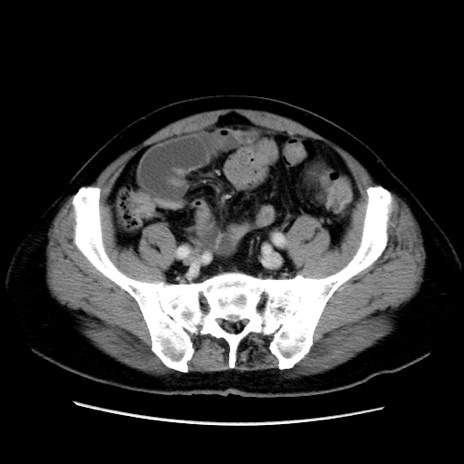

症例16(横断像)

【症例】 70歳代男性

【主訴】 腹痛、嘔吐

【現病歴】 約1ヶ月前より間欠的に腹痛と嘔吐あり、当院消化器内科を受診したところCTで多発する肝臓のLDAを指摘され、精査中であった。以降は消化器症状は安定していたが、2日前より嘔気と腹痛があり、同日より排便・排ガスが消失した。改善認めず、 本日、救急外来を受診した。

【既往歴】 大腸ポリープ切除後。

【身体所見】意識清明・会話良好、BT 36.3℃、BP 127/80mmHg、 P 80bpm、腹部:膨満あり、平坦・軟、上腹部正中および下腹部正中に圧痛あり、反跳痛なし、筋性防御なし。

【データ】WBC 7200、CRP 0.77